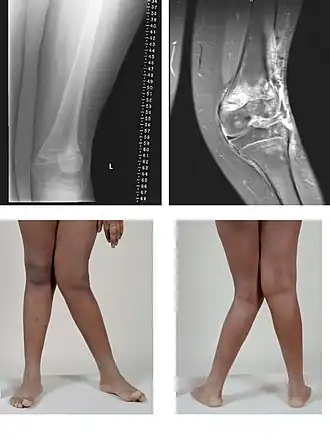

Rotura de meniscos

El menisco se lesiona generalmente por un mecanismo de rotación, cuando la rodilla se encuentra en situación de semiflexión y con el pie apoyado. En estas circunstancias, al producirse la rotación, el cóndilo del fémur presiona directamente al menisco y este se rompe o fisura. Esta lesión afecta con mayor frecuencia al menisco interno o medial que al externo. Las roturas pueden llegar a ser de una gravedad significativa. Se dividen en horizontales, verticales, transversales, oblicuas o mixtas. El diagnóstico se basa en la presencia de síntomas y signos clínicos característicos, en los hallazgos reportados por la resonancia magnética y artroscopia. Esta última puede ser al mismo tiempo diagnóstica y terapéutica.[20]

Rotura de los ligamentos cruzados

La rotura del ligamento cruzado anterior es una lesión frecuente. Puede producirse durante la actividad deportiva por giros enérgicos de la rodilla en los que el pie permanece en fuerte contacto con el suelo. El mecanismo lesional suele asociarse a semiflexión, valgo y rotación externa de la articulación de la rodilla. En el momento en que se sufre esta lesión suele sentirse un dolor intenso y una sensación de chasquido. En condiciones normales el ligamento cruzado anterior sirve de freno para evitar un movimiento anterior excesivo de la tibia con respecto al fémur. El médico puede realizar pruebas exploratorias como la Prueba del cajón y la Prueba de Lachman que si son positivas hacen más probable este diagnóstico. Su confirmación se obtiene mediante la resonancia magnética o artroscopia.[23] En la lesión combinada, conocida como triada de O'Donoghue o rodilla desgraciada, se suman la rotura del ligamento cruzado anterior, del ligamento lateral interno y del menisco interno.[24]

Genu valgum

El eje formado por el fémur y la pierna es más abierto de lo normal, adoptando el miembro inferior un aspecto en X con las rodillas muy juntas y los talones separados. Puede estar presente desde la infancia o aparecer en la vida adulta, muy frecuentemente causado por sobrepeso u obesidad.

Genu varum

En esta deformidad los miembros inferiores tienen una convexidad externa y los cóndilos femorales internos están separados por una distancia superior a los 6 cm. Es por lo tanto una desviación inversa a la que se produce en el genu valgum. Se describe a veces como miembros inferiores en paréntesis, pues los pies están muy próximos y las rodillas separadas en situación de bipedestación (de pie).